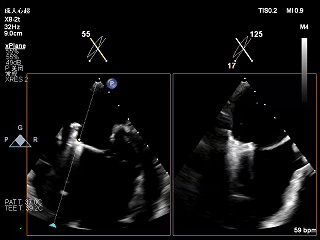

术前Bicom切面

术前X-Plane

术前瓣口面积5.39cm²

后叶长度9.24cm

可用房间隔穿刺高度4.03cm